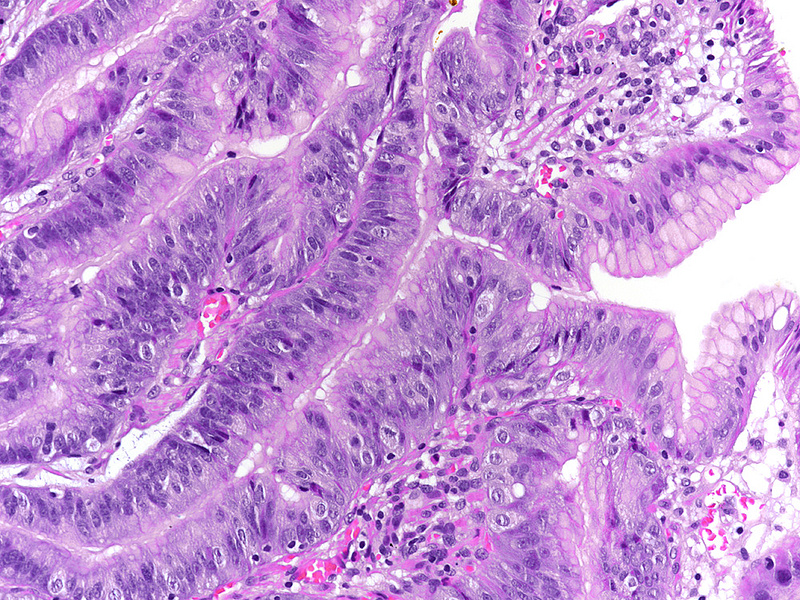

Upon histology, the three polyps showed a similar morphology. The polyps demonstrated irregularly shaped, branching, papillary projections with well-vascularized stroma (Panels A-C). On higher magnification, these projections were lined by dysplastic columnar cells, with hyperchromatic, enlarged and stratified nuclei and a distinctive apical mucin cap, prompting diagnosis of foveolar-type gastric adenoma with low-grade dysplasia (Panels D-F). The background tissue showed non-atrophic oxyntic mucosa, without gastritis, Helicobacter pylori infection or intestinal metaplasia. In summary, the histology was consistent with the newly described variant of foveolar-type adenoma with a raspberry-like appearance.